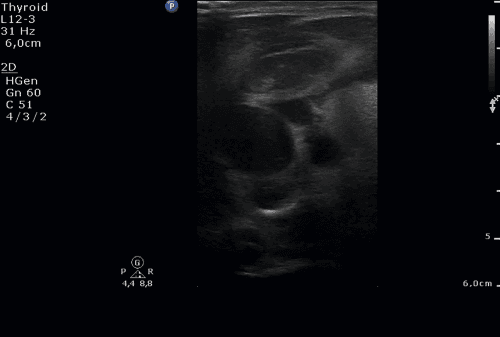

Chłopiec 10-letni został przyjęty z powodu utrzymującej się od 3 dni gorączki do 39°C z towarzyszącymi bólami brzucha oraz wymiotami. Przy przyjęciu w badaniu fizykalnym z odchyleń od normy zaobserwowano powiększone węzły chłonne szyjne i podżuchwowe, zaczerwienienie gardła; brzuch był miękki, nieco tkliwy przy palpacji w nadbrzuszu środkowym. W badaniach laboratoryjnych stwierdzono: w morfologii krwi obwodowej przewagę limfocytów, podwyższenie transaminaz oraz nieznaczne narastanie parametrów stanu zapalnego (OB, CRP, PCT). W wykonanym badaniu ultra-sonograficznym jamy brzusznej – hepatosplenomegalia. W USG szyi uwidoczniono obustronne odczynowe powiększenie węzłów chłonnych (największy po stronie prawej do 42 x 15 mm). Węzły chłonne w tym przypadku były zmienione zapalnie i cechowały się w badaniu ultrasonograficznym zwiększonym wymiarem, ale zachowanymi proporcjami (kształt owalny), zatartą wnęką, nieco zmniejszoną echogennością części obwodowej oraz zwiększonym odwnękowym unaczynieniem. Węzły te układały się w postaci konglomeratów – widoczne były wyraźne granice między poszczególnymi węzłami chłonnymi (w odróżnieniu od pakietów). W badaniach mikrobiologicznych uzyskano dodatnie miano przeciwciał w kierunku EBV VCA/EA IgM oraz EBV VCA/EA IgG. Rozpoznano mononukleozę zakaźną. Zastosowano leczenie objawowe. W tym przypadku był to obraz ostrego zapalenia węzłów chłonnych. W przebiegu przewlekłego zapalenia węzły limfatyczne różnią się od prawidłowych jedynie wielkością (są większe), a unaczynienie nie jest tak obfite jak w stanach ostrych. Węzły chłonne prawidłowe oraz odczynowe mają niskooporowe spektrum przepływu RI < 0,7.